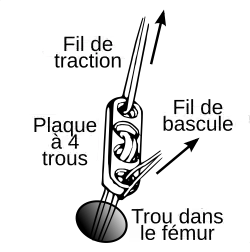

L'endobouton est tiré avec le transplant à travers le trou par le fil de traction, et ensuite fixé en tirant sur le fil de bascule.

Consolidation du transplant

Au début des années 1990, les transplants de tendons patellaires étaient fixés avec des vis d'interférence en titane soit aux deux bouts du transplant, soit uniquement au tibia, et fixés au fémur par un endobouton, enfilé sur le transplant. L'endobouton consiste en une bride de fil non résorbable munie d'une tête basculante en titane (plaque à quatre trous), que l'on bascule après un enfilage à travers le canal dans l'os[240]. Plus tard, on a utilisé des bioscrews (vis d'interférence résorbables) à la place des vis en titane[241], pour rendre une nouvelle opération d'enlèvement des vis inutile. Ces vis sont faites de polymères décomposables, comme un polylactide : Poly-L-lactide ou PLLA, ou poly-L-co-D/L-lactide ou PLDLLA. On peut aussi utiliser une technique hybride de vis résorbables (fixation intra-articulaire) et d'endobouton (fixation extra-articulaire). Dans la Press-Fit-Technik-Fixation, qui naît vers 1995, on peut complètement abandonner la fixation par les vis dans la technique BTB. Les extrémités osseuses sont usinées en cône, si bien qu'un bord-à-bord solide dans les canaux forés est possible. En 1996, on a utilisé des fraises commandées par robot pour faire ce joint, mais ce procédé n'a pu s'imposer en raison de son coût (en personnel et en appareils) et du manque de résultats indiscutablement meilleurs en opération.

Pour les transplants semi-tendineux et gracile (STG), on utilise le plus souvent des vis biodégradables pour la fixation. Depuis la fin des années 1990, on utilise aussi dans ce cas une fixation sans implantation[242]. Dans cette technique, le transplant semi-tendineux et gracile est noué à un bout. Le canal fémoral est creusé 4 mm plus étroit du côté articulation que de l'autre côté. Le transplant est alors introduit dans l'articulation à travers le canal fémoral. Là, le nœud du transplant se coince avant la partie plus étroite. Les mesures ont montré que la rigidité de l'articulation et la charge maximale atteignent des valeurs semblables à celles d'autres techniques. Par le nœud des bouts du tendon, les vis d'interférence deviennent superflues. Les partisans de cette fixation sans vis y voient un avantage de coût. Comme on n'utilise pas de vis, il ne peut pas y avoir de problème avec leurs matériaux[242]. Un inconvénient est cependant le canal significativement plus grand dans le fémur[1].

Pour la fixation des transplants avec des vis d'interférence, il est important que la fixation soit effectuée tout près des surfaces articulaires pour éviter l’effet bungee (le bungee est le saut à l'élastique ; dans le cas présent, il faut éviter que l’élasticité du tendon amène à des frottements longitudinaux contre l'os et à son usure) et l'effet d'essuie-glace (même remarque pour les frottements transversaux à la sortie de l'os)[243].